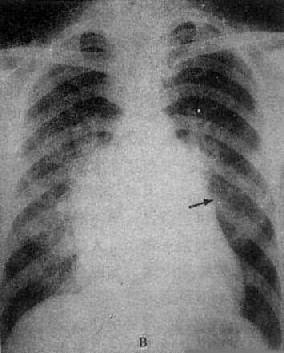

图3-2-15 二尖瓣狭窄

A.右前斜位:右心室增大,肺动脉段突出(↑),心前间隙变窄(↑),左心房轻度增大;B.后前位:心增大,呈二尖瓣型,右心室增大,肺动脉段突出,左心耳增大,出现第三弓(↓),有肺瘀血表现;C.左前斜位:右心室增大,左心房增大不明显;左心室不增大。

图3-2-16 二尖瓣关闭不全并狭窄

心增大呈二尖瓣型,右心室增大,肺动脉

段突出,左心耳增大,有肺瘀血